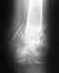

Вальгусный вколоченный перелом. Смещение некритичное, жить можно. Оперировать большой необходимости нет. Достаточно косыночной повязки на 4 недели.